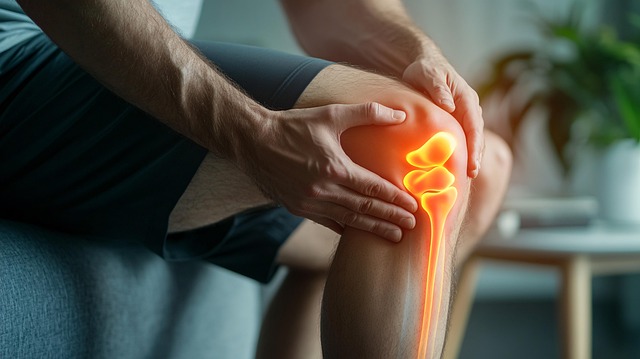

4. 다리 움직임 제한

고관절의 가동 범위가 줄어들며 특정 각도로 다리를 움직일 때 통증이 발생할 수 있습니다. 이는 고관절 유연성 저하와 관련이 있으며, 근육과 인대의 긴장도 영향을 미칠 수 있습니다.